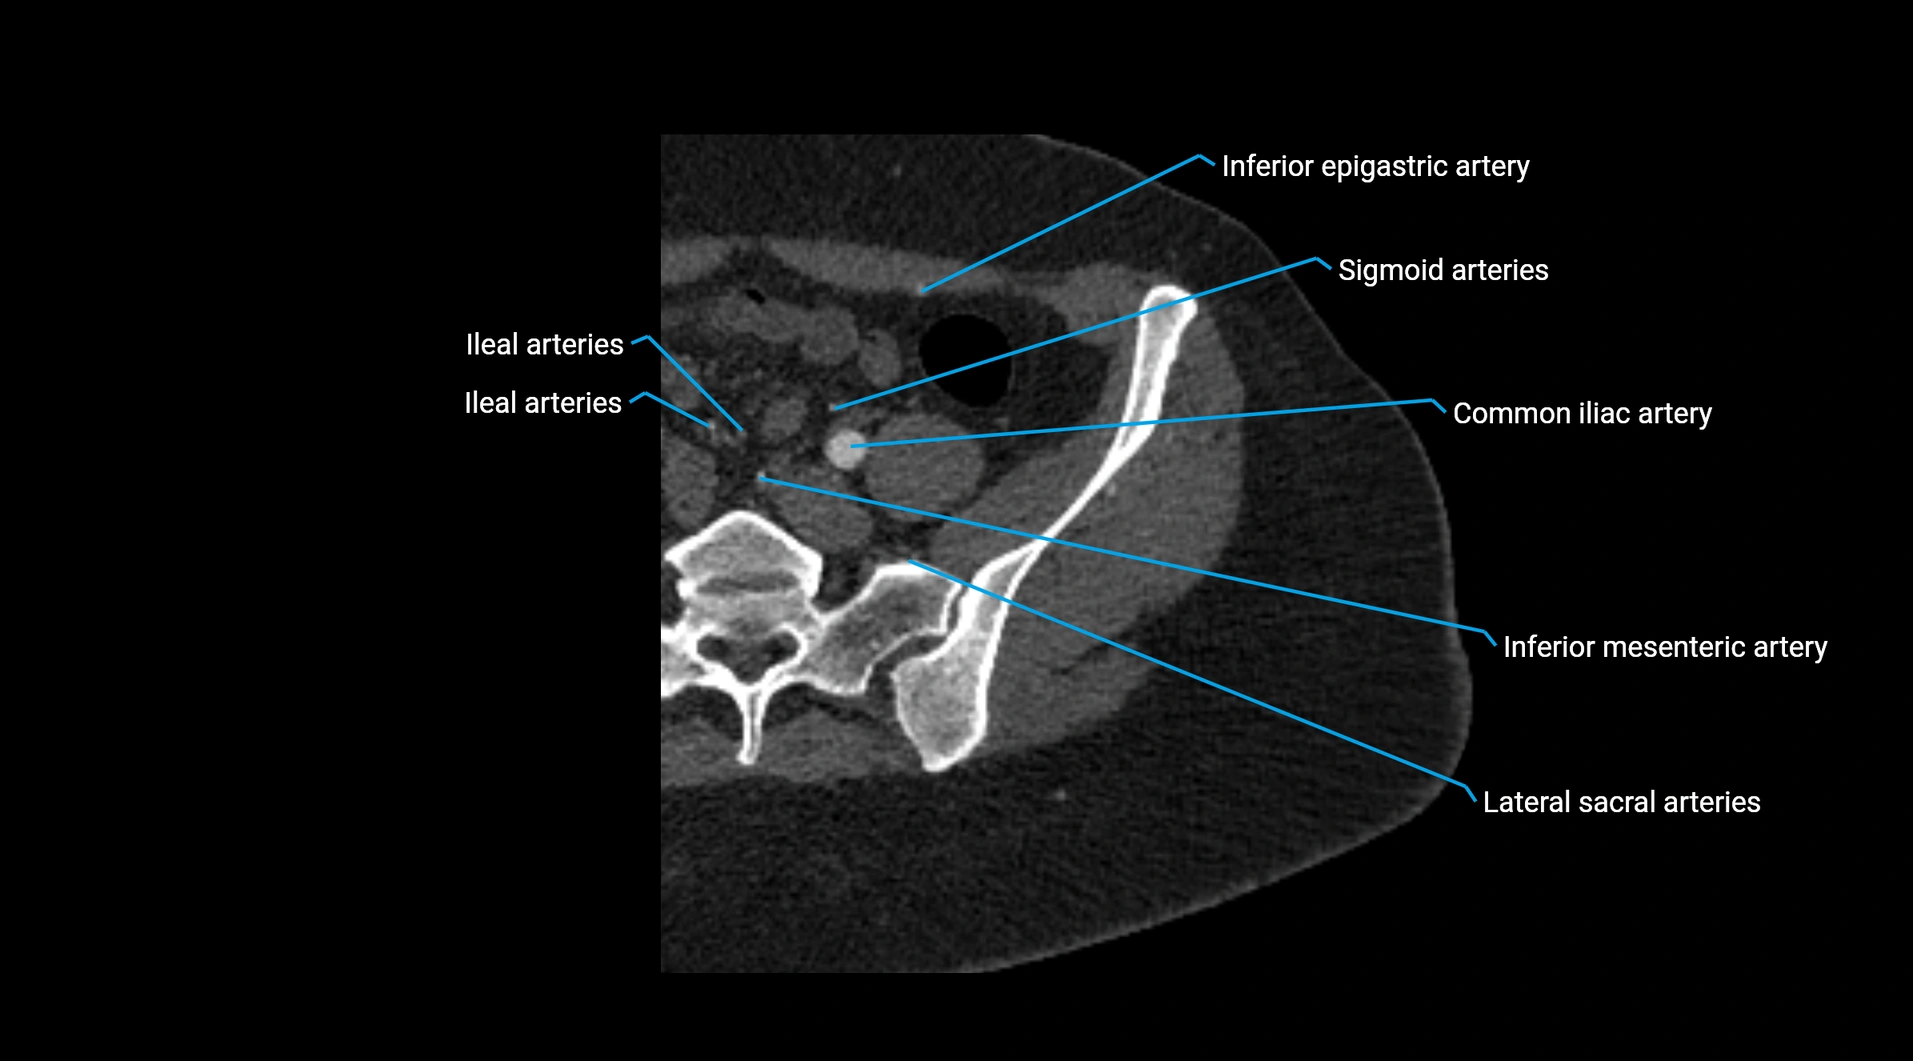

CT images

image

Contrast-enhanced CT (CTA):

• Gold standard for abdominal aortic imaging

• Provides excellent detail of lumen, wall, aneurysm, thrombus, and branch vessels

• Multiplanar and 3D reconstructions help in aneurysm measurement, stent graft planning, and dissection evaluation

• Unpaired visceral branches: celiac trunk, superior mesenteric artery (SMA), inferior mesenteric artery (IMA)

• Paired visceral branches: middle suprarenal arteries, renal arteries, gonadal arteries (testicular or ovarian)

• Parietal branches: inferior phrenic arteries, lumbar arteries, median sacral artery

• Terminal branches: right and left common iliac arteries